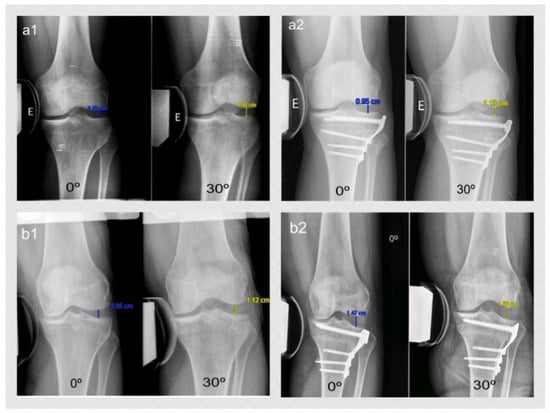

Figure 2. Varus-stress radiological image at full extension and 30° of knee flexion in a patient randomized to Group 1 (a1 pre-op; a2 post-op) and in Group 2 (b1 pre-op; b2 post-op). The measurement was done between the central aspect of the lateral femoral condyle and the corresponding lateral tibial plateau.

The lateral stress radiograph was performed at full extension and 30° of flexion on both knees while applying a 15 KPa load with a TELOS-stress device. The gapping distance in the lateral compartment was defined as the closest perpendicular distance (in millimeters) between the central aspect of the lateral femoral condyle and the corresponding lateral tibial plateau (Figure 2). For this purpose, the thickness of the articular cartilage surface was not considered [12]. An expert orthopedic radiologist who was not involved in the study did these measurements pre-operatively and 1 year post-operatively.